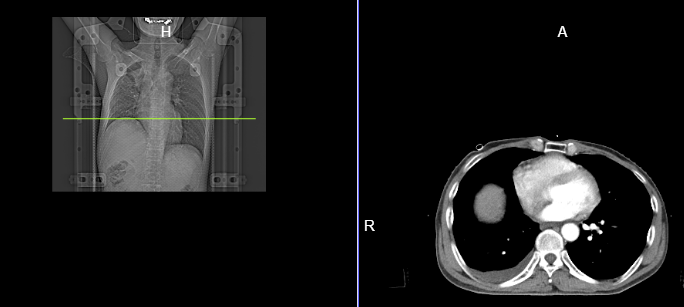

咳嗽、胸闷、气短 30年老烟民不相信自己会得肺癌 近日,医院来了一名50岁的王先生,述说自己间断性咳嗽、咳痰1年多,最近一个月感觉自己胸闷气短症状加剧,于是去当地医院检查,考虑为右肺气胸,随后行胸腔闭式引流术,排空气体后,王先生胸闷气短症状并没得到缓解。 于是到上一级医院进一步治疗,通过纤支镜检查时发现右主支气管有肿物,活检检查显示为鳞状细胞癌,并随即行气管支架植入术。但术后没多久再次出现气胸,如此反反复复,王先生很是苦恼,甚至不相信自己患了肺癌,认为自己又没咳血,怎么就会是肺癌啦? 其实肺是一个哑巴器官,很多时候早期肺癌并不会向身体报警,但如果你同时出现下面这些症状,就要提高警惕,及时检查! 1、胸部感染并且伴随有长期反复感染的症状; 2、无缘无故地喘息和呼吸急促; 3、胸部或肩部疼痛,并且长期没有好转; 4、嗓音嘶哑并且持续三周以上; 5、长期咳嗽、体重减轻、感觉极度疲倦; 7、杵状手指:手指末端形状发生改变,出现变大或变圆的症状; 8、脸部、颈部、腋下出现肿胀; 久治不愈的肺癌症状 在放射治疗下销声匿迹 “命途多舛”王先生为寻求更好的治疗方法,经多方打听,找到了在肺癌治疗方面颇有造诣的昆明医科肿瘤医院骆建华主任团队,寻求进一步诊治。 骆主任在详细了解王先生病情之后,评估患者气道肿瘤暂无手术条件,凭借自己多年来熟用放射治疗救治患者的丰富经验,为王先生治疗了详细的放疗计划。 放疗结束后,王先生咳嗽、胸闷、气短等不适情况明显好转,恢复状态良好。通过CT影像资料显示,在放射治疗的帮助下,王先生的肺部肿瘤已得到有效控制。 放疗前 放疗后 科普小结 放疗在肺癌治疗中大有可为 由于王先生肿瘤位置的特殊性,手术不但不能一劳永逸,还存在巨大风险,这种情况下,选择放射治疗的确是一个明智的决定。 近年来,随着科技高速发展,放疗在肺癌的临床应用中有着不可替代的作用,其“高精度、高剂量、高疗效、低损伤”的特点,能够追着肿瘤细胞“指哪打哪”。 特别适合高龄、不具备手术条件或其他因素身体耐受力差的患者,可通过放疗减轻患者痛苦、延长患者生存时间、降低复发及远处转移的风险,并且还能大大缩短患者平均住院日,减少患者住院费用,为广大肿瘤患者提供了新的希望!